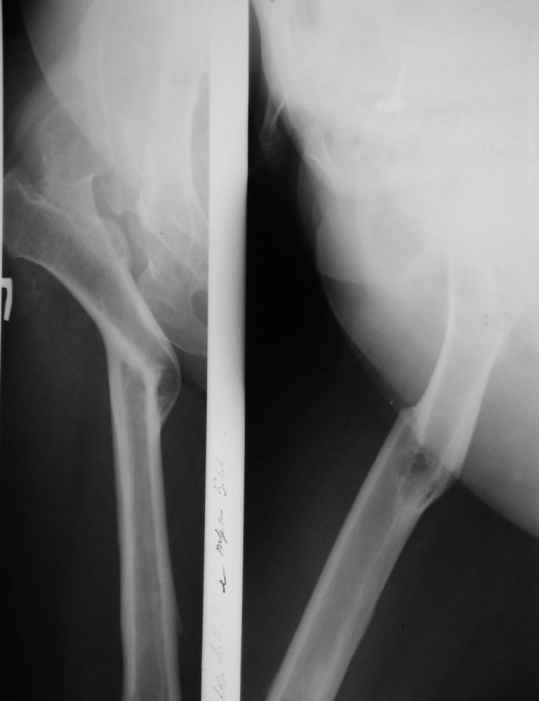

В прищепке случай 1999 года - эндопротезирование после операции Шанца-Илизарова. Возраст пациентки 45. Коррекция была в 17 лет. А Рыков Хабаровск.